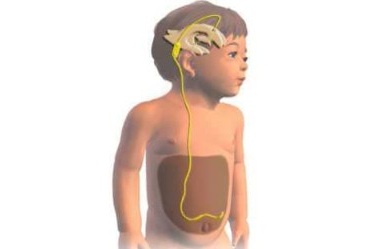

Вентрикуло-перитонеальный шунт: Показания и применение

Раздел: Фотоальбом решений